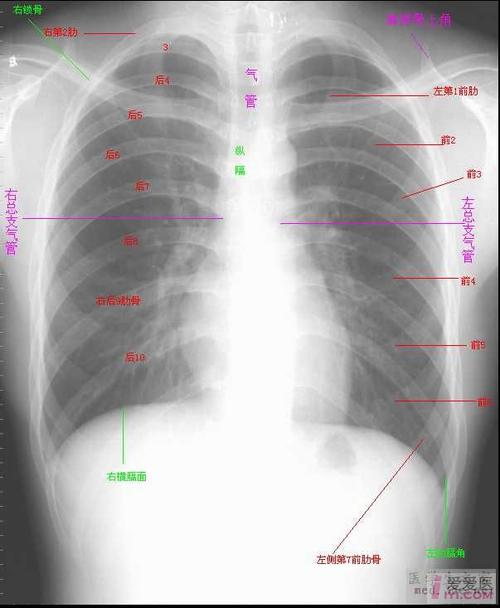

肺门角,肺纹理

胸廓对称,气管居中,纵隔影不宽,肺门影不大,双肺纹理清晰(增强)

注意 左侧肺门常略高于右

下后肺静脉干5.右下肺动脉 6.肺门角 7.中间支气管 8.右上肺静脉 9.